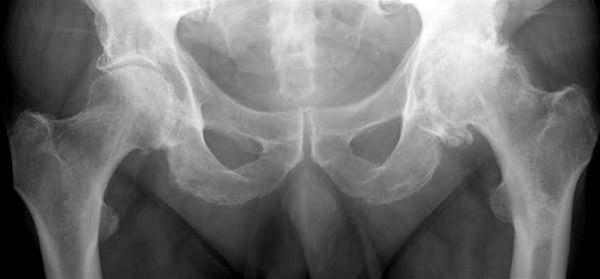

Betydelig mer artroseforandringer i venstre hofteledd.Hofteleddet består av hofteskåla, som er en del av bekkenbeinet og lårbeinets hoftekule. Både hofteskålen og hoftekulen er "kledd" med glatt brusk som sikrer at bevegelser foregår med minst mulig motstand.

På den ene siden ser man ofte artroseforandringer i flere ledd på røntgen hos godt voksne og eldre, men bare en del av disse har symptomer på artrose i disse leddene. På den andre siden er det ikke uvanlig at tidlige artroseforandringer hos voksne med symptomer ikke vises på røntgen.